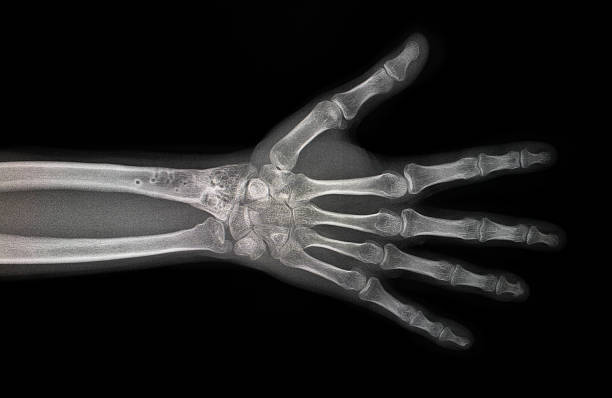

2. 영상 검사

기본적인 엑스레이 검사와 초음파 검사를 통해 관절과 뼈의 이상 여부와 손상 정도를 확인합니다. 엑스레이는 관절 소금의 상태를 보여주며, 초음파 검사는 관절의 부종 정도를 확인하고 관절 주위 조직에서 발생한 손상을 판별하는 데 도움이 됩니다.